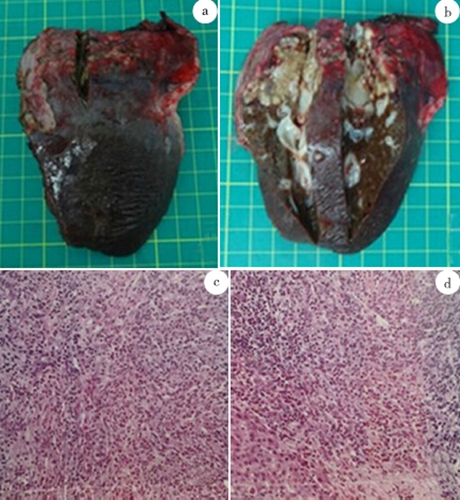

膽管癌圖片

小細胞膽管癌

肝內膽管癌